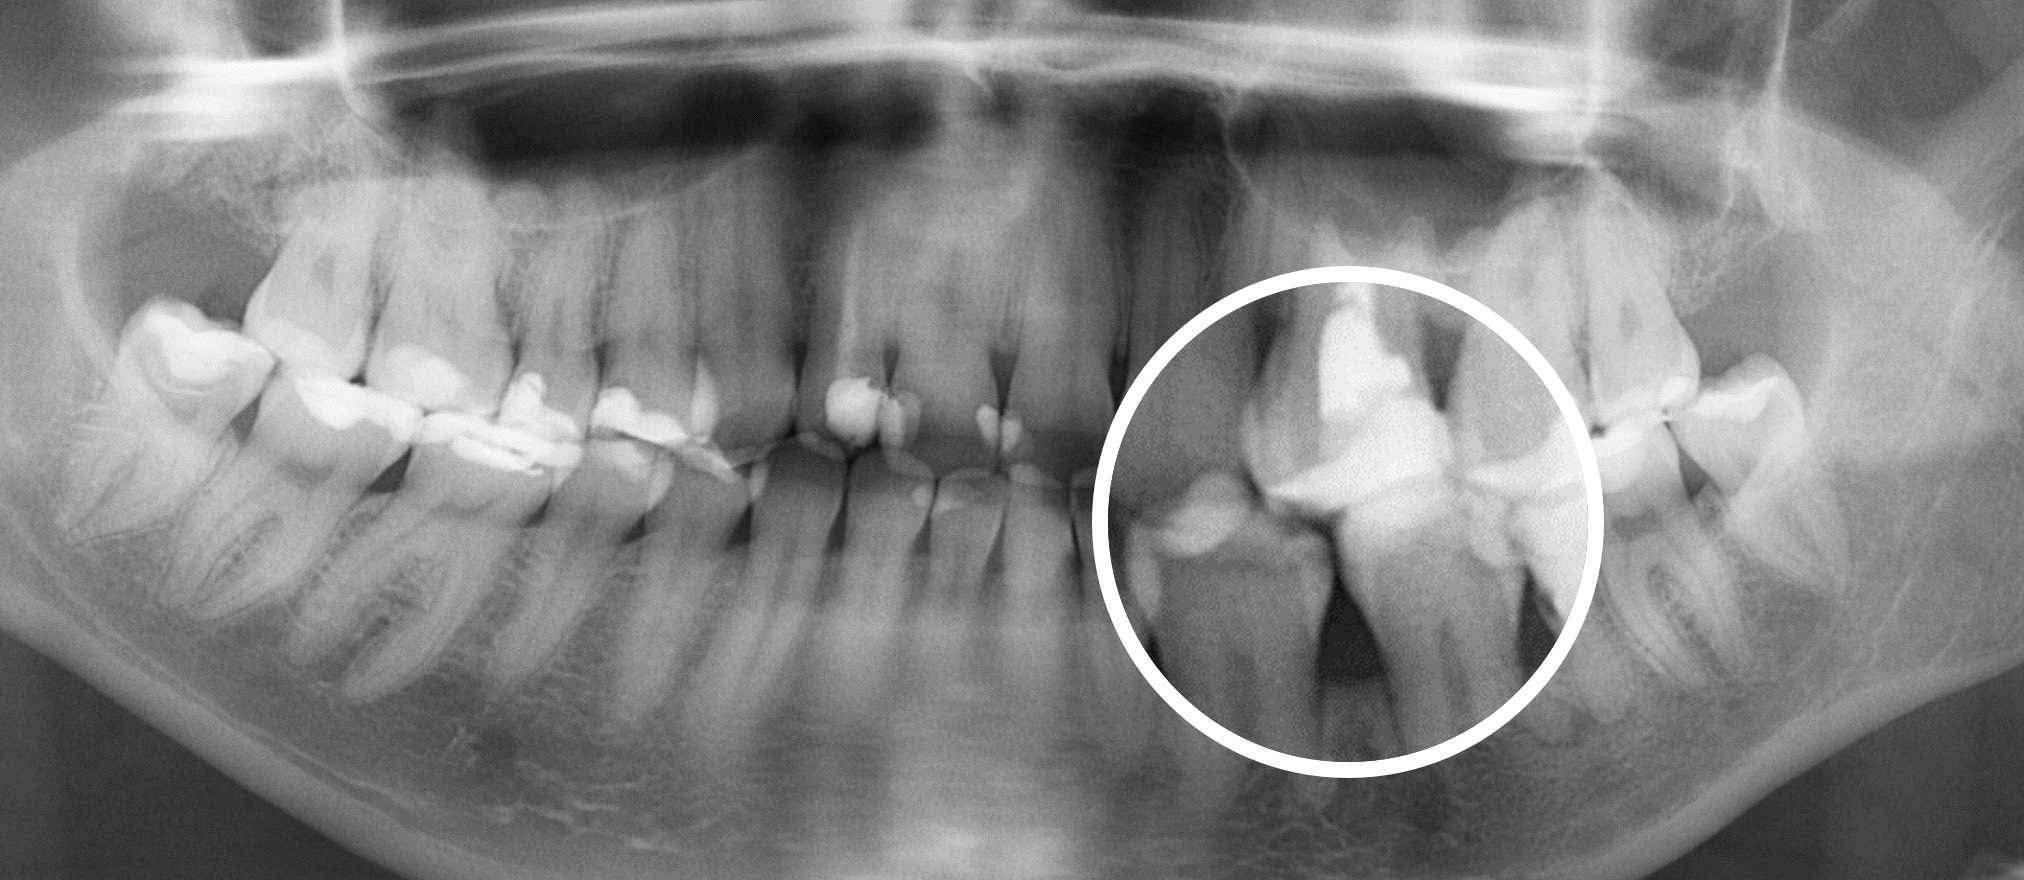

Сравнение 2D и 3D снимков

3D снимки — это новый уровень диагностики. Но при их появлении возникла достаточно большая сложность.

Дело в том, что 3D снимки гораздо более информативны, чем 2D снимки, но на их чтение требуется гораздо больше времени и более высокая квалификация стоматолога, это гораздо более трудоемкий процесс.

Далеко не каждый стоматолог, умеет правильно читать КТ снимки, для этого требуется отдельное обучение. Также стоматологам не хватало времени выделяемого на прием, чтобы проанализировать каждый зуб.

Что привело к тому, что комплексность диагностики начала страдать. Врачи успевали проанализировать только 1-2 зуба за прием.